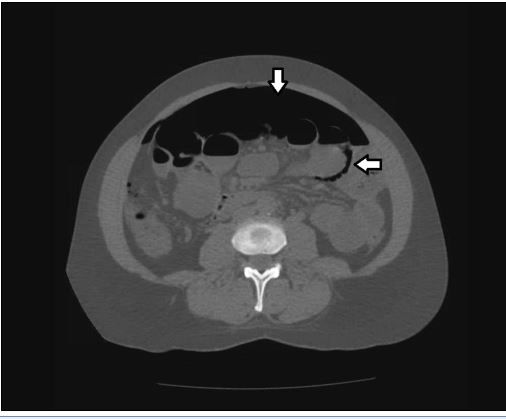

CT scans of the patient’s chest, abdomen, and pelvis further detailed the pneumoperitoneum and showed intraluminal free air alongside gravity-defying intramural air in the small intestine, although there were no signs of perforation (Figure 2). Of note, the radiographs revealed esophageal stricture with proximal dilatation in addition to pneumoperitoneum, consistent with the patient’s diagnosis of scleroderma (Figure 3).

Radiographic findings of air collections within the wall of the patient’s intestines established pneumatosis cystoides intestinalis (PCI) as the cause of her spontaneous pneumoperitoneum. The combination of a benign abdomen on examination, the absence of any other explanation for pneumoperitoneum, and the presence of the typical findings for PCI in a patient with scleroderma fully supported this diagnosis.

The diagnosis of PCI is primarily radiological; the test of choice is abdominal CT scan. Common findings include linear or bubbly intramural gas patterns parallel to the bowel wall, often gravity-defying and in circular arrangement on cross-section, as was seen on our patient’s CT scan. Positive radiological findings are lacking in about one-third of patients; follow-up histology can confirm the diagnosis but usually is unnecessary.4